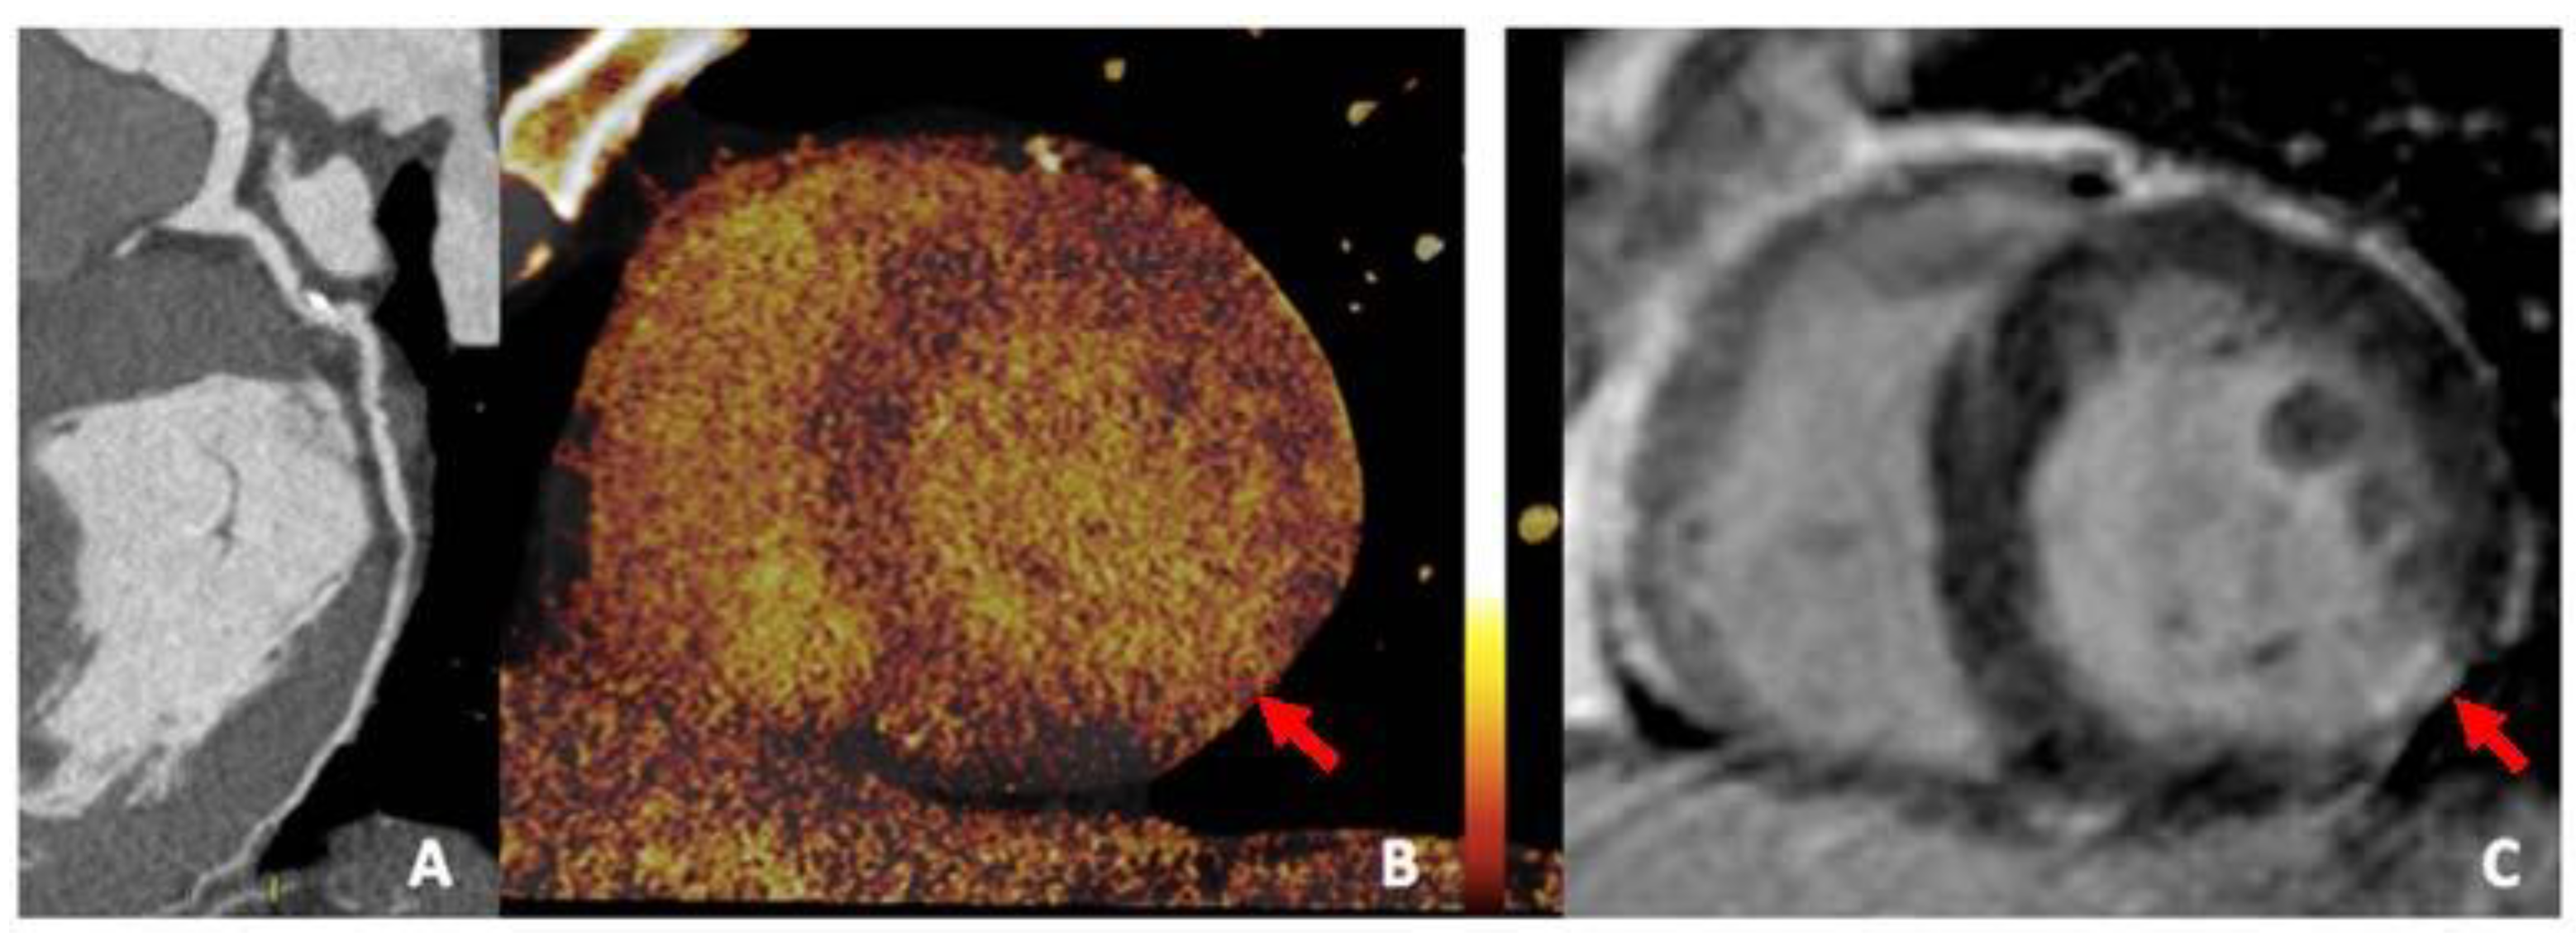

3.4. Iodine Perfusion Maps